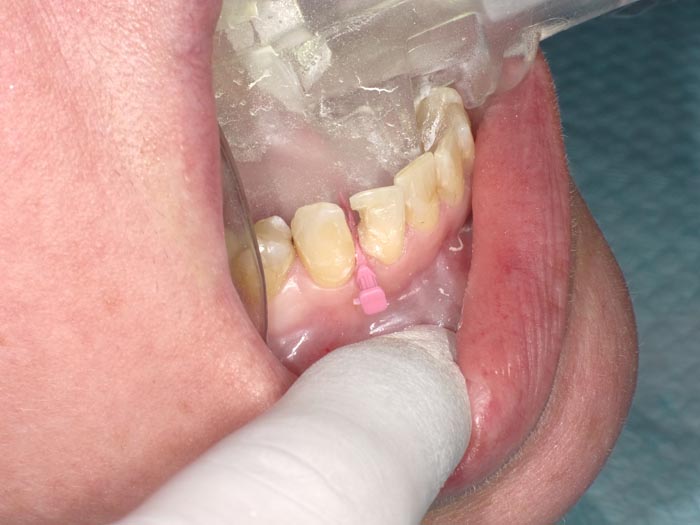

Case 1

A 37-year-old patient presented for treatment after years of neglect. After administering anesthetic and placing an Isolite isolation device, we prepared teeth #10–12 and restored them

with Activa Bioactive-Restorative composite.

• Figure 1

• Figure 2

• Figure 3

• Figure 4

• Figure 5

• Figure 6